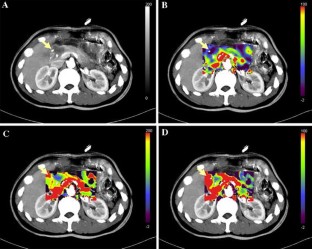

The aim of this study is to summarize the experience of preoperative diagnosis for nonfunctioning pancreatic neuroendocrine tumors (NFPNETs). The medical records of patients with NFPNETs were identified from 2001 to 2009 in a single center. They were all reviewed and analyzed for their demographics, clinical presentation, preoperative laboratory evaluation and radiographic characterization. Twenty-six patients (11 men and 15 women) in the past 8 years were diagnosed with NFPNETs. Almost all patients had the normal level of exocrine tumor markers. Although it was not difficult to find tumors by traditional imaging modalities including CT and MRI, the misdiagnosis rate was as high as 81.2%. Perfusion CT was helpful to predict the biological behavior of tumors and even identified NFPNETs as benign or malignant. The preoperative diagnosis for NFPNETs can be confirmed by one or the combination of CgA, perfusion CT, FNA-EUS, PET and octreoscans. NFPNETs should be aroused suspicion of normal exocrine tumor markers and relative specific imaging appearance, which can be proved by one or the combination of CgA, perfusion CT, FNA-EUS, PET and octreoscans.

Fig. 2